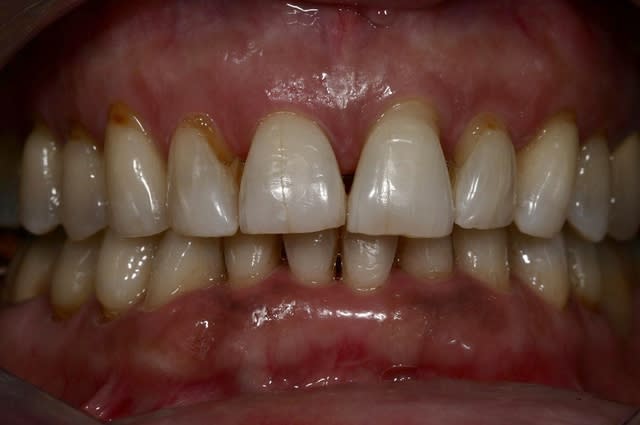

pour terminer avec ma patiente qui initia ce post:

aprés blanchiment.